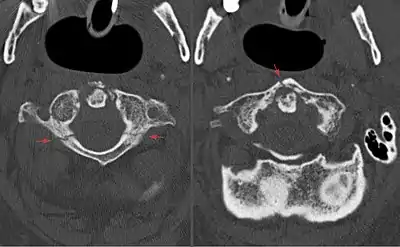

| Image of the first cervical vertebra, which is broken during a Jefferson fracture | |